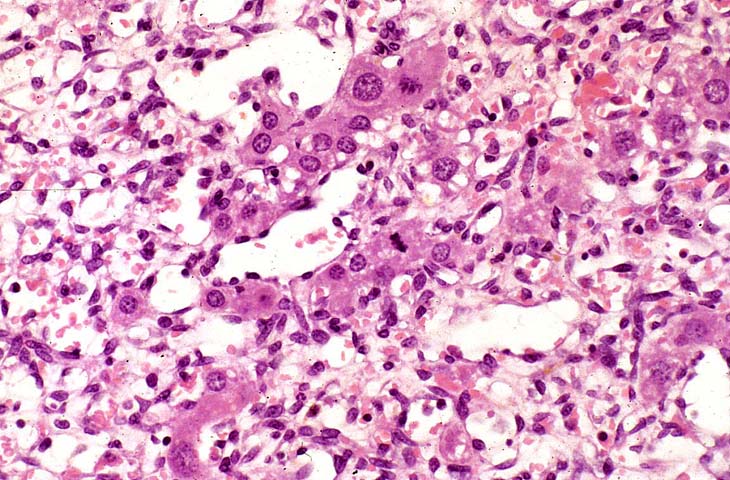

An Ito cell tumor that has replaced much of the normal hepatic parenchyma without distorting the normal contour of the liver; higher magnification shows fat-filled and stellate cells in the hepatic sinusoids.

The proliferating stellate cells have a myxomatous appearance in some areas and have caused atrophy of hepatic cords.